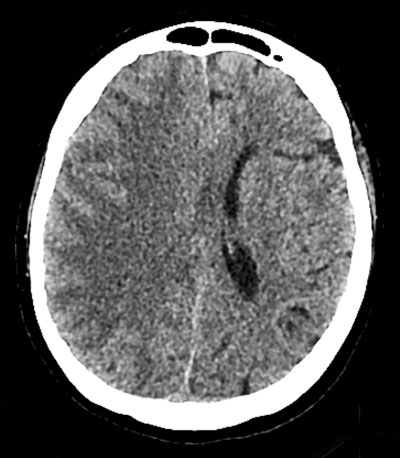

Eftersom patienten fortfarande befann sig i dator­tomografen utfördes undersökning med DT-hjärna/

torax, vilken visade multipla lågattenuerande förändringar i höger hjärnhemisfär, vilka initialt tolkades som fettembolier (Figur 1). Eftergranskning av bilderna från DT-torax visade betydande mängder luft i aorta (Figur 2), vilket dock inte sågs initialt.

Figur 1 (patient 1). DT-hjärna klockan 10.54 visar ett flertal runda lågattenuerande förändringar inom höger hemisfär (luftbubblor). Luft kan ses även i andra snitt från samma undersökning, vilket innebär en massiv cerebral arteriell embolisering. Erfarenheten från flera fall som diagnostiserades på Karolinska universitetssjukhuset under en 20-årspe­riod visar dominans av högersidiga luftembolier, vilket sannolikt beror på truncus brachiocephalicus anatomiska läge.